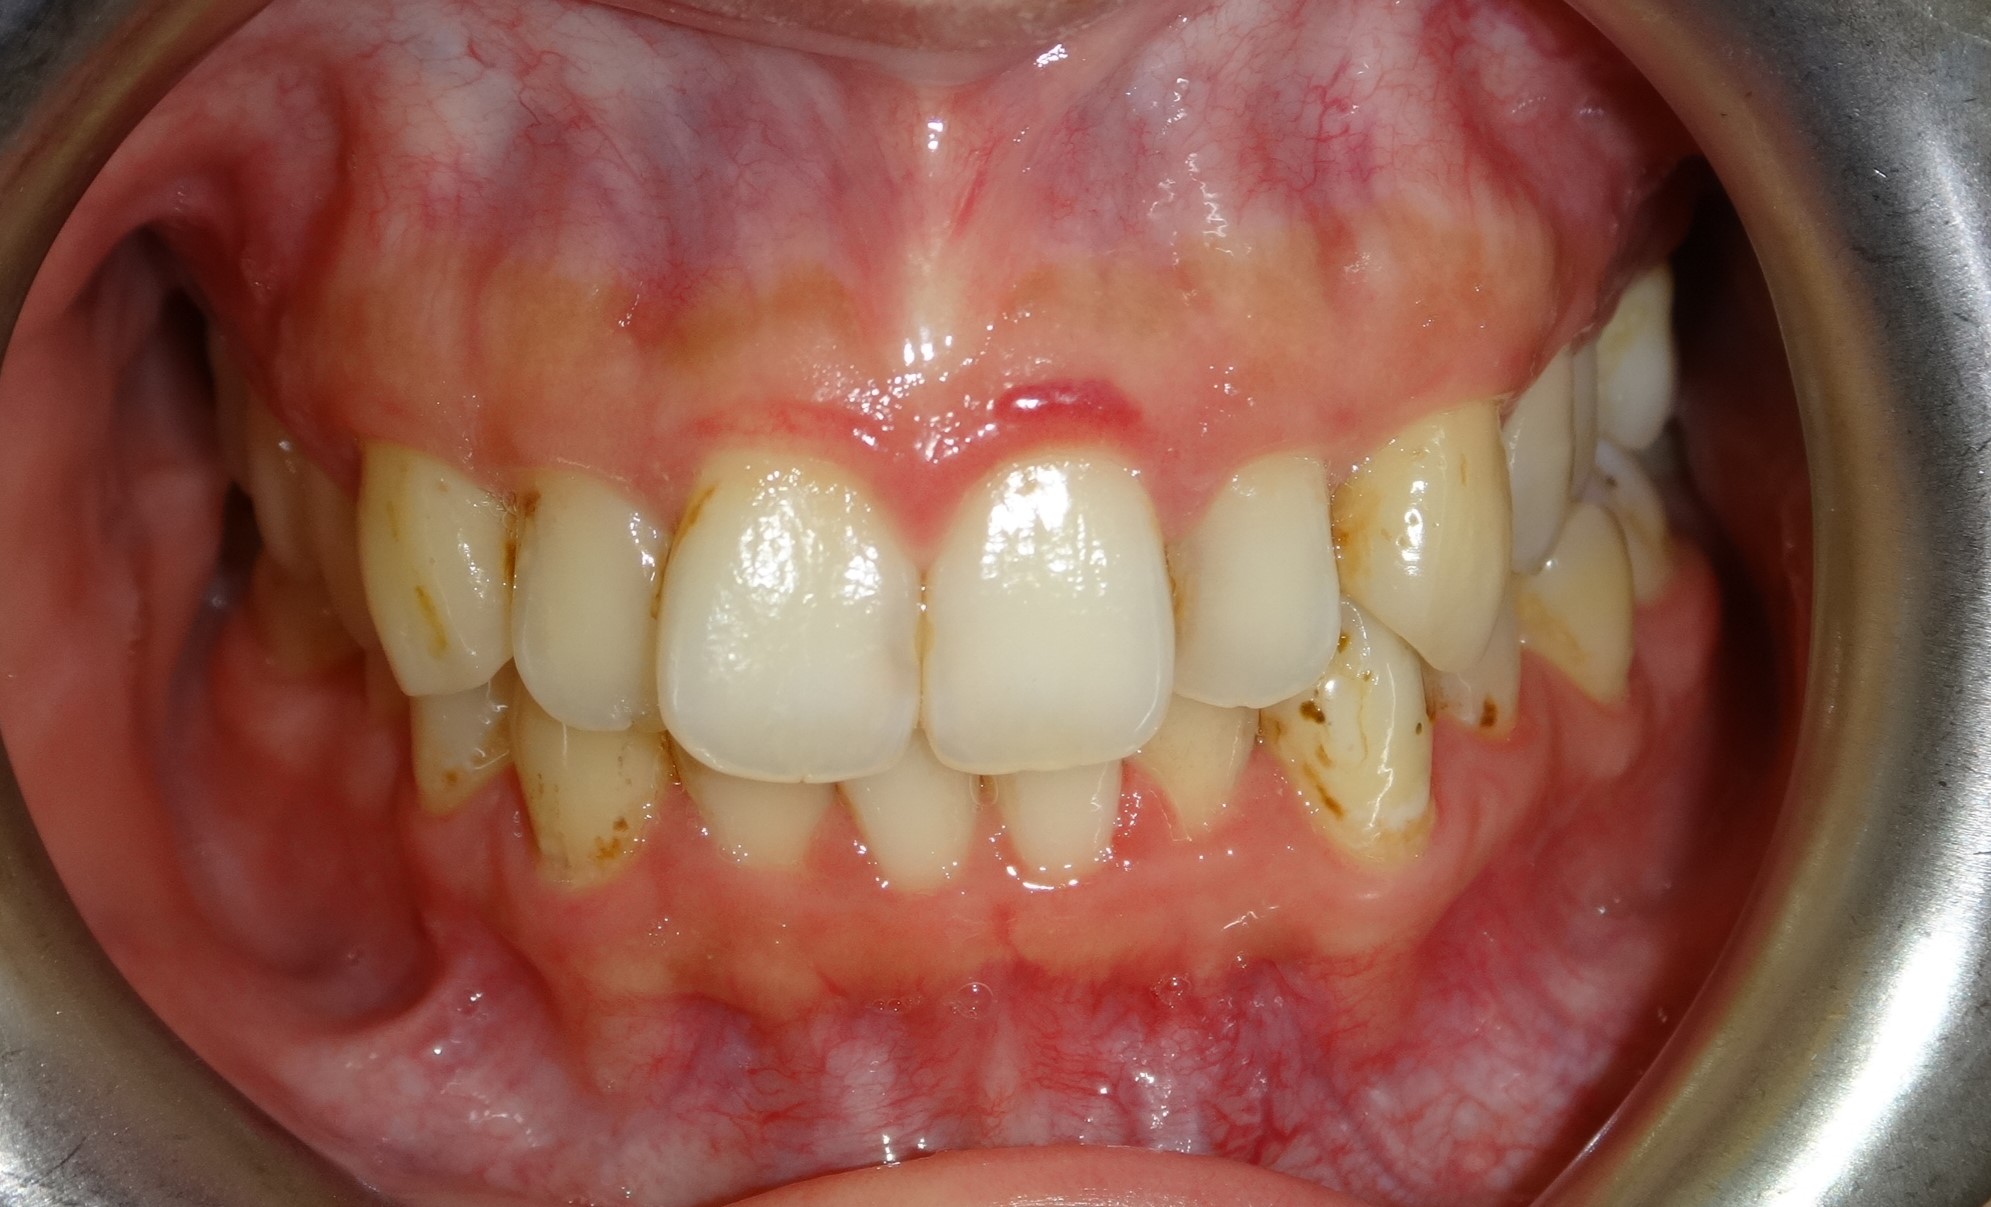

微矯正案例 首頁 案例分享 齒顎矯正 微矯正案例 矯正前 矯正後 - 不拔牙案例 - 年紀:29歲 矯正方式:隱適美隱形矯正 時間:18個月 矯正訴求:門牙外凸、中線不正 聲明:本所療程皆由專業醫生評估後,依照個人口腔狀況進行治療。因每位患者個別狀況不同,術後狀況也不盡相同,需親來本所由醫生評估。